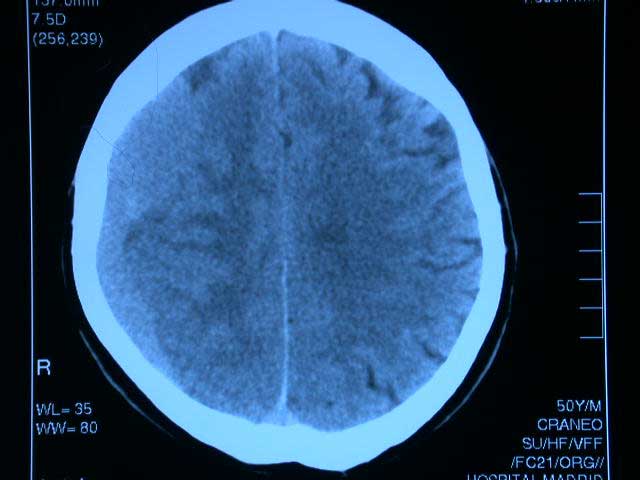

Fármacos antitrombóticos y hematoma subdural

El uso creciente de fármacos anticoagulantes y antiagregantes se asocia a un aumento de hematomas subdurales, especialmente en los mayores de 75 años. La combinación de antagonistas de vitamina K con antiplaquetarios potencia el riesgo. JAMA, 28 de febrero de 2017